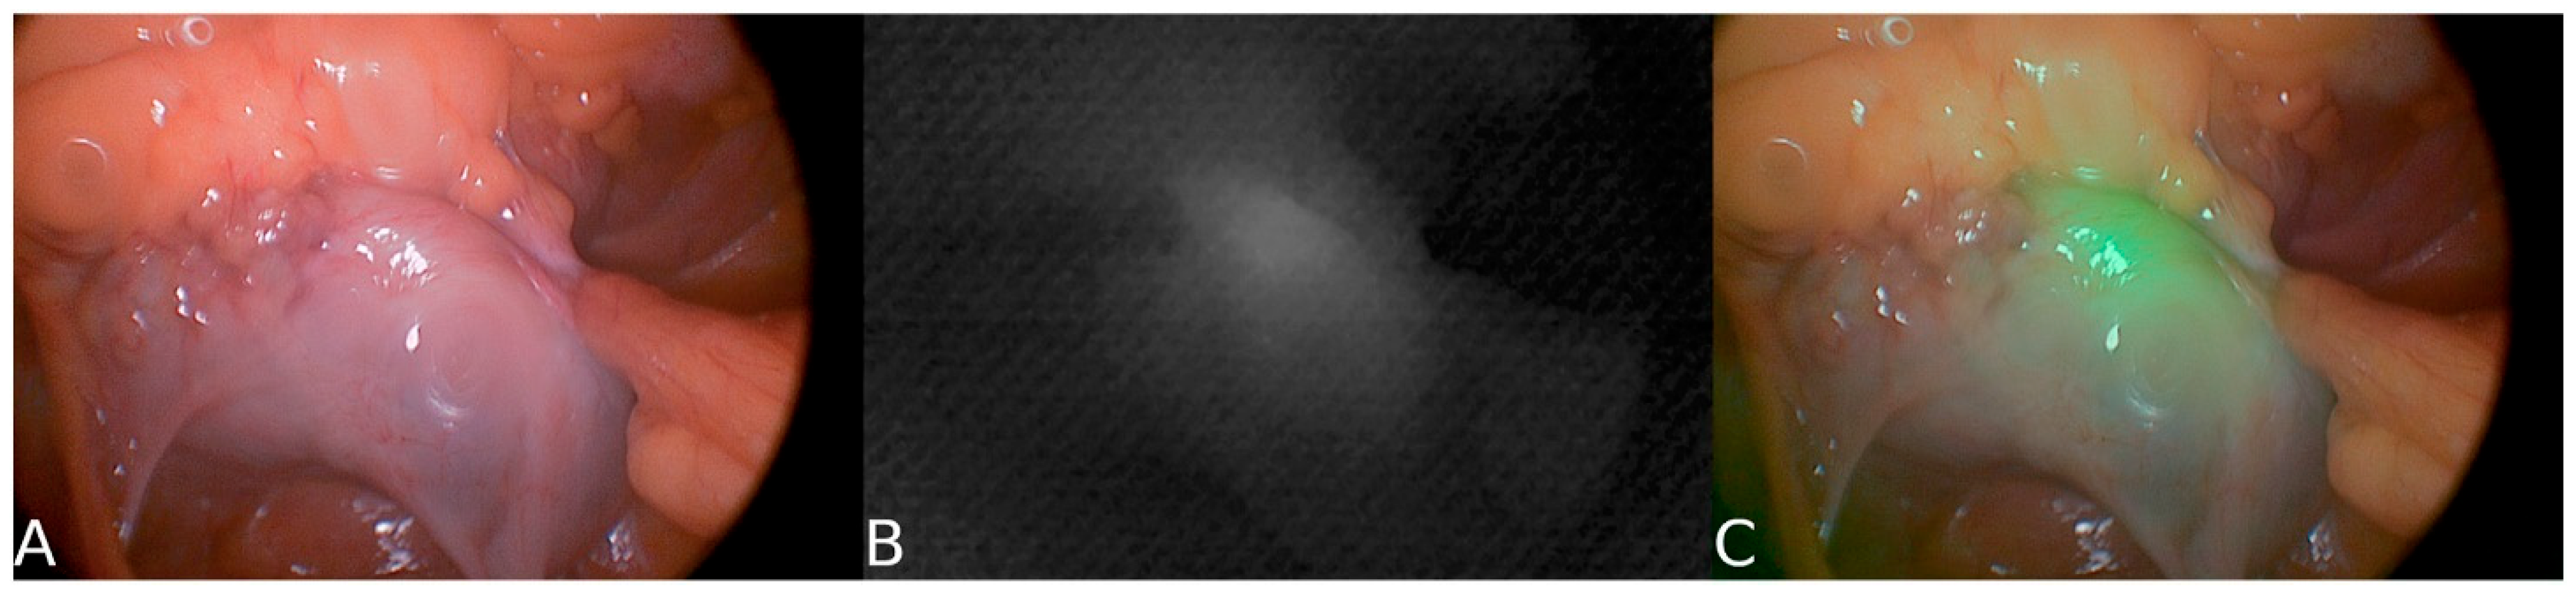

| Near-Infrared Fluorescence (NIR) | Uses ICG or targeted agents for real-time visualization | Improves intraoperative nerve visibility | [41,53] |

- Jin, H.; Zheng, L.; Lu, L.; Cui, M. Near-infrared intraoperative imaging of pelvic autonomic nerves: A pilot study. Surg. Endosc. 2022, 36, 2349–2356. [Google Scholar] [CrossRef] [PubMed]

| Hypogastric nerve (HGN) | ~93% | ~81% | Plexus-level visible | MRN has a higher POV; NIR aids in plexus contrast. | [37,41] |

| Pelvic plexus / IHP (PP) | ~65% | ~44% | SBR ≈ 3.18 | MRN > intraop POV; NIR improves real-time contrast. | [37,41] |